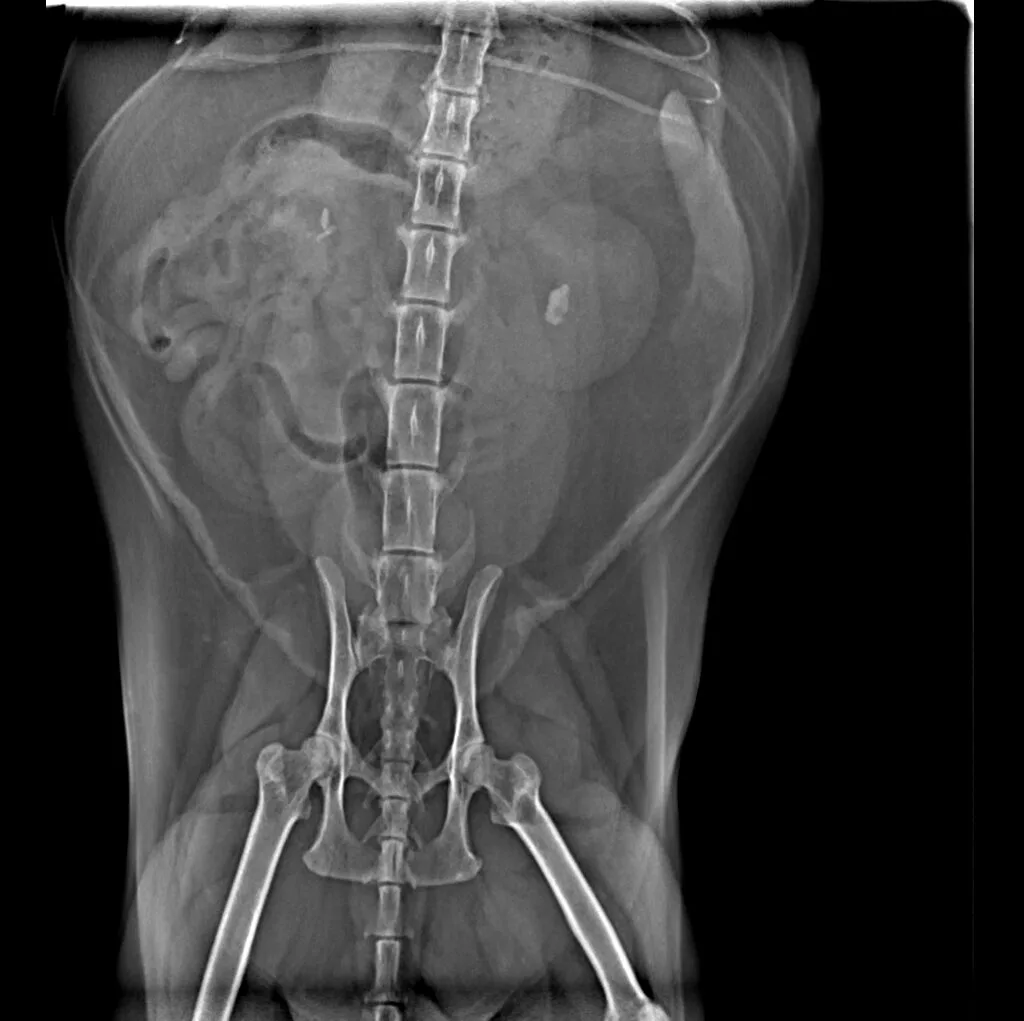

At Grand Ave. Pet Hospital, we utilize digital radiography to diagnose and monitor a wide range of medical conditions in pets. Digital X-rays provide clearer images, faster results, and safer radiation levels, ensuring the best possible care for your furry companion.

Digital radiography offers superior imaging quality and precision compared to traditional X-ray techniques. It allows us to detect hidden health issues early, leading to faster and more effective treatments.

🔹 Abdominal & Gastrointestinal Issues – Detecting obstructions, tumors, or organ abnormalities